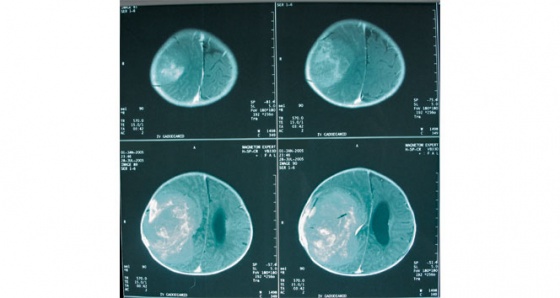

Çocuklardaki belirti ve bulgular erişkinlere göre atipiktir. Bu nedenle tanı geç konabilir ve geçen süre içerisinde kafatası içindeki tümör de büyük hacim veya boyutlara varabilir. Ağırlıklı olarak kafatası arka çukuru orta hatta yerleşim gösterirler ve çoğu zaman beyin omurilik sıvı dolaşımını bozarak beyinde sıvı toplanması (hidrosefali) bulguları ile belirti verirler” dedi.

Bazen de genel hastalıklarda görülebilen süregelen halsizlik, huzursuzlukta bu belirtilere eklenebiliyor. Ultrasonografi, bilgisayarlı tomografi (BT), manyetik rezonans görüntüleme (MRG) gibi tanı yöntemlerinden yararlanılarak teşhis konan hastalık, multidisipliner takip ve tedavi gerektiriyor.